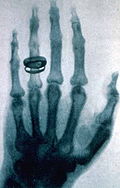

- January 5 - An Austrian newspaper reports that Wilhelm Röntgen discovered a type of radiation later known as X-rays.

- January 12 - H.L. Smith takes the first X-ray photograph.

- January 18 - The X-ray machine is exhibited for the first time.